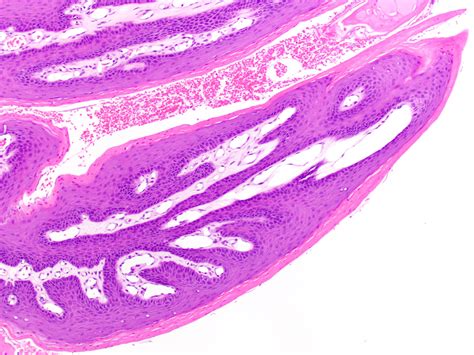

An Oral Squamous Papilloma is a benign, exophytic growth resulting from an infection caused by the Human Papillomavirus (HPV), most commonly types 6 and 11. Unlike malignant tumors, these papillomas are non-cancerous and do not have the potential to spread to other parts of the body (metastasize). They typically appear as solitary, painless, white-to-pink lesions with a roughened, pebbly surface.

Identifying an Oral Squamous Papilloma often involves observing its distinct morphology. Clinicians look for specific visual cues that differentiate this lesion from other oral pathologies like focal epithelial hyperplasia or squamous cell carcinoma. Because they are exophytic, they grow outward from the surface, often resembling a small cluster of grapes or a delicate cauliflower head.

• Biopsy: The gold standard for diagnosis. A small sample of the tissue is removed and examined under a microscope to confirm the presence of koilocytes—cells characteristic of HPV infection.